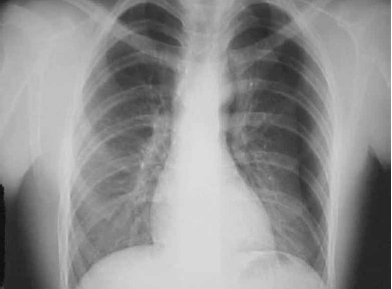

Homem de 38 anos deu entrada no Pronto-Socorro trazido por amigos, com relato de ferimento por arma branca em região do tronco à esquerda, após briga em um bar. Não houve atendimento pré-hospitalar. Chegou após 15 minutos do episódio e apresentava-se alcoolizado, agitado, reagindo a dor, com dificuldade para respirar e inspirações profundas e pausadas. Exame físico: ferimento penetrante por arma branca, de 6 cm de extensão em hemitórax esquerdo, no 6º EIC, com linha axilar média com presença de traumatopneia. Inspirações profundas e com pausas e uso de musculatura acessória. Presença de enfisema subcutâneo, diminuição da expansibilidade com hipertimpanismo à percussão e ausência de MV em HTE. FR = 24 mrpm . Saturação O2: 75%. PA: 115/74 mmHg. FC: 122 bpm. RX tórax demonstrado.

(www.bibliomed.com.br)